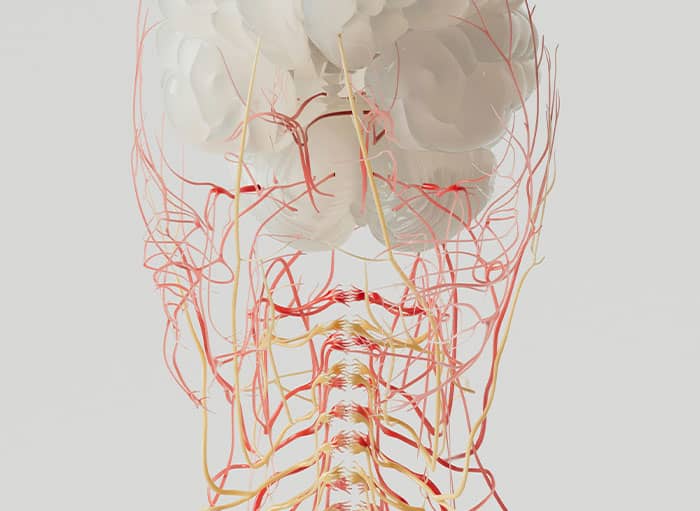

The brain pulsates in sync with your heartbeat.

It’s a rhythmic, constant movement – it’s actually BEAUTIFUL.

Real brain tissue is softer, more fragile, and surprisingly watery. It can be torn or injured just by suction or light pressure.

But what I admire and am astonished the most is that

every person’s brain is wired differently. Actual locations of speech, movement, or memory can vary person to person. That’s why we do brain mapping during surgeries. It’s pretty cool , like exploring unknown… And shows how unique humans are.